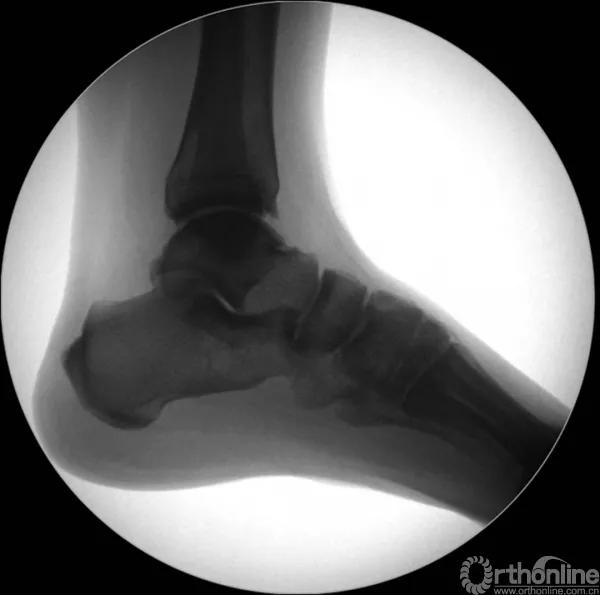

X线诊断:标准的踝关节影像学评估应包括3个位相:前后位(图5),踝穴位(内旋15°)(图6),侧位(图7)。

图7 侧位

当踝关节严重损伤时内外踝及距骨将发生不同程度的移位(图8)。有时外踝骨折会伴有三角韧带的损伤,静态的X线摄片并不能准确地反映踝关节的稳定性,应力位片及MRI检查可完善对踝关节稳定性及韧带损伤的评估(图9)。此时应通过患肢损伤机制及放射资料准确判断踝关节损伤的类型以正确指导复位和固定。有时单纯内踝骨折可能是更为复杂的“Maisonneuve骨折”的一部分,该骨折还包括腓骨近端骨折及韧带联合损伤,故X线检查应投照整个胫腓骨。